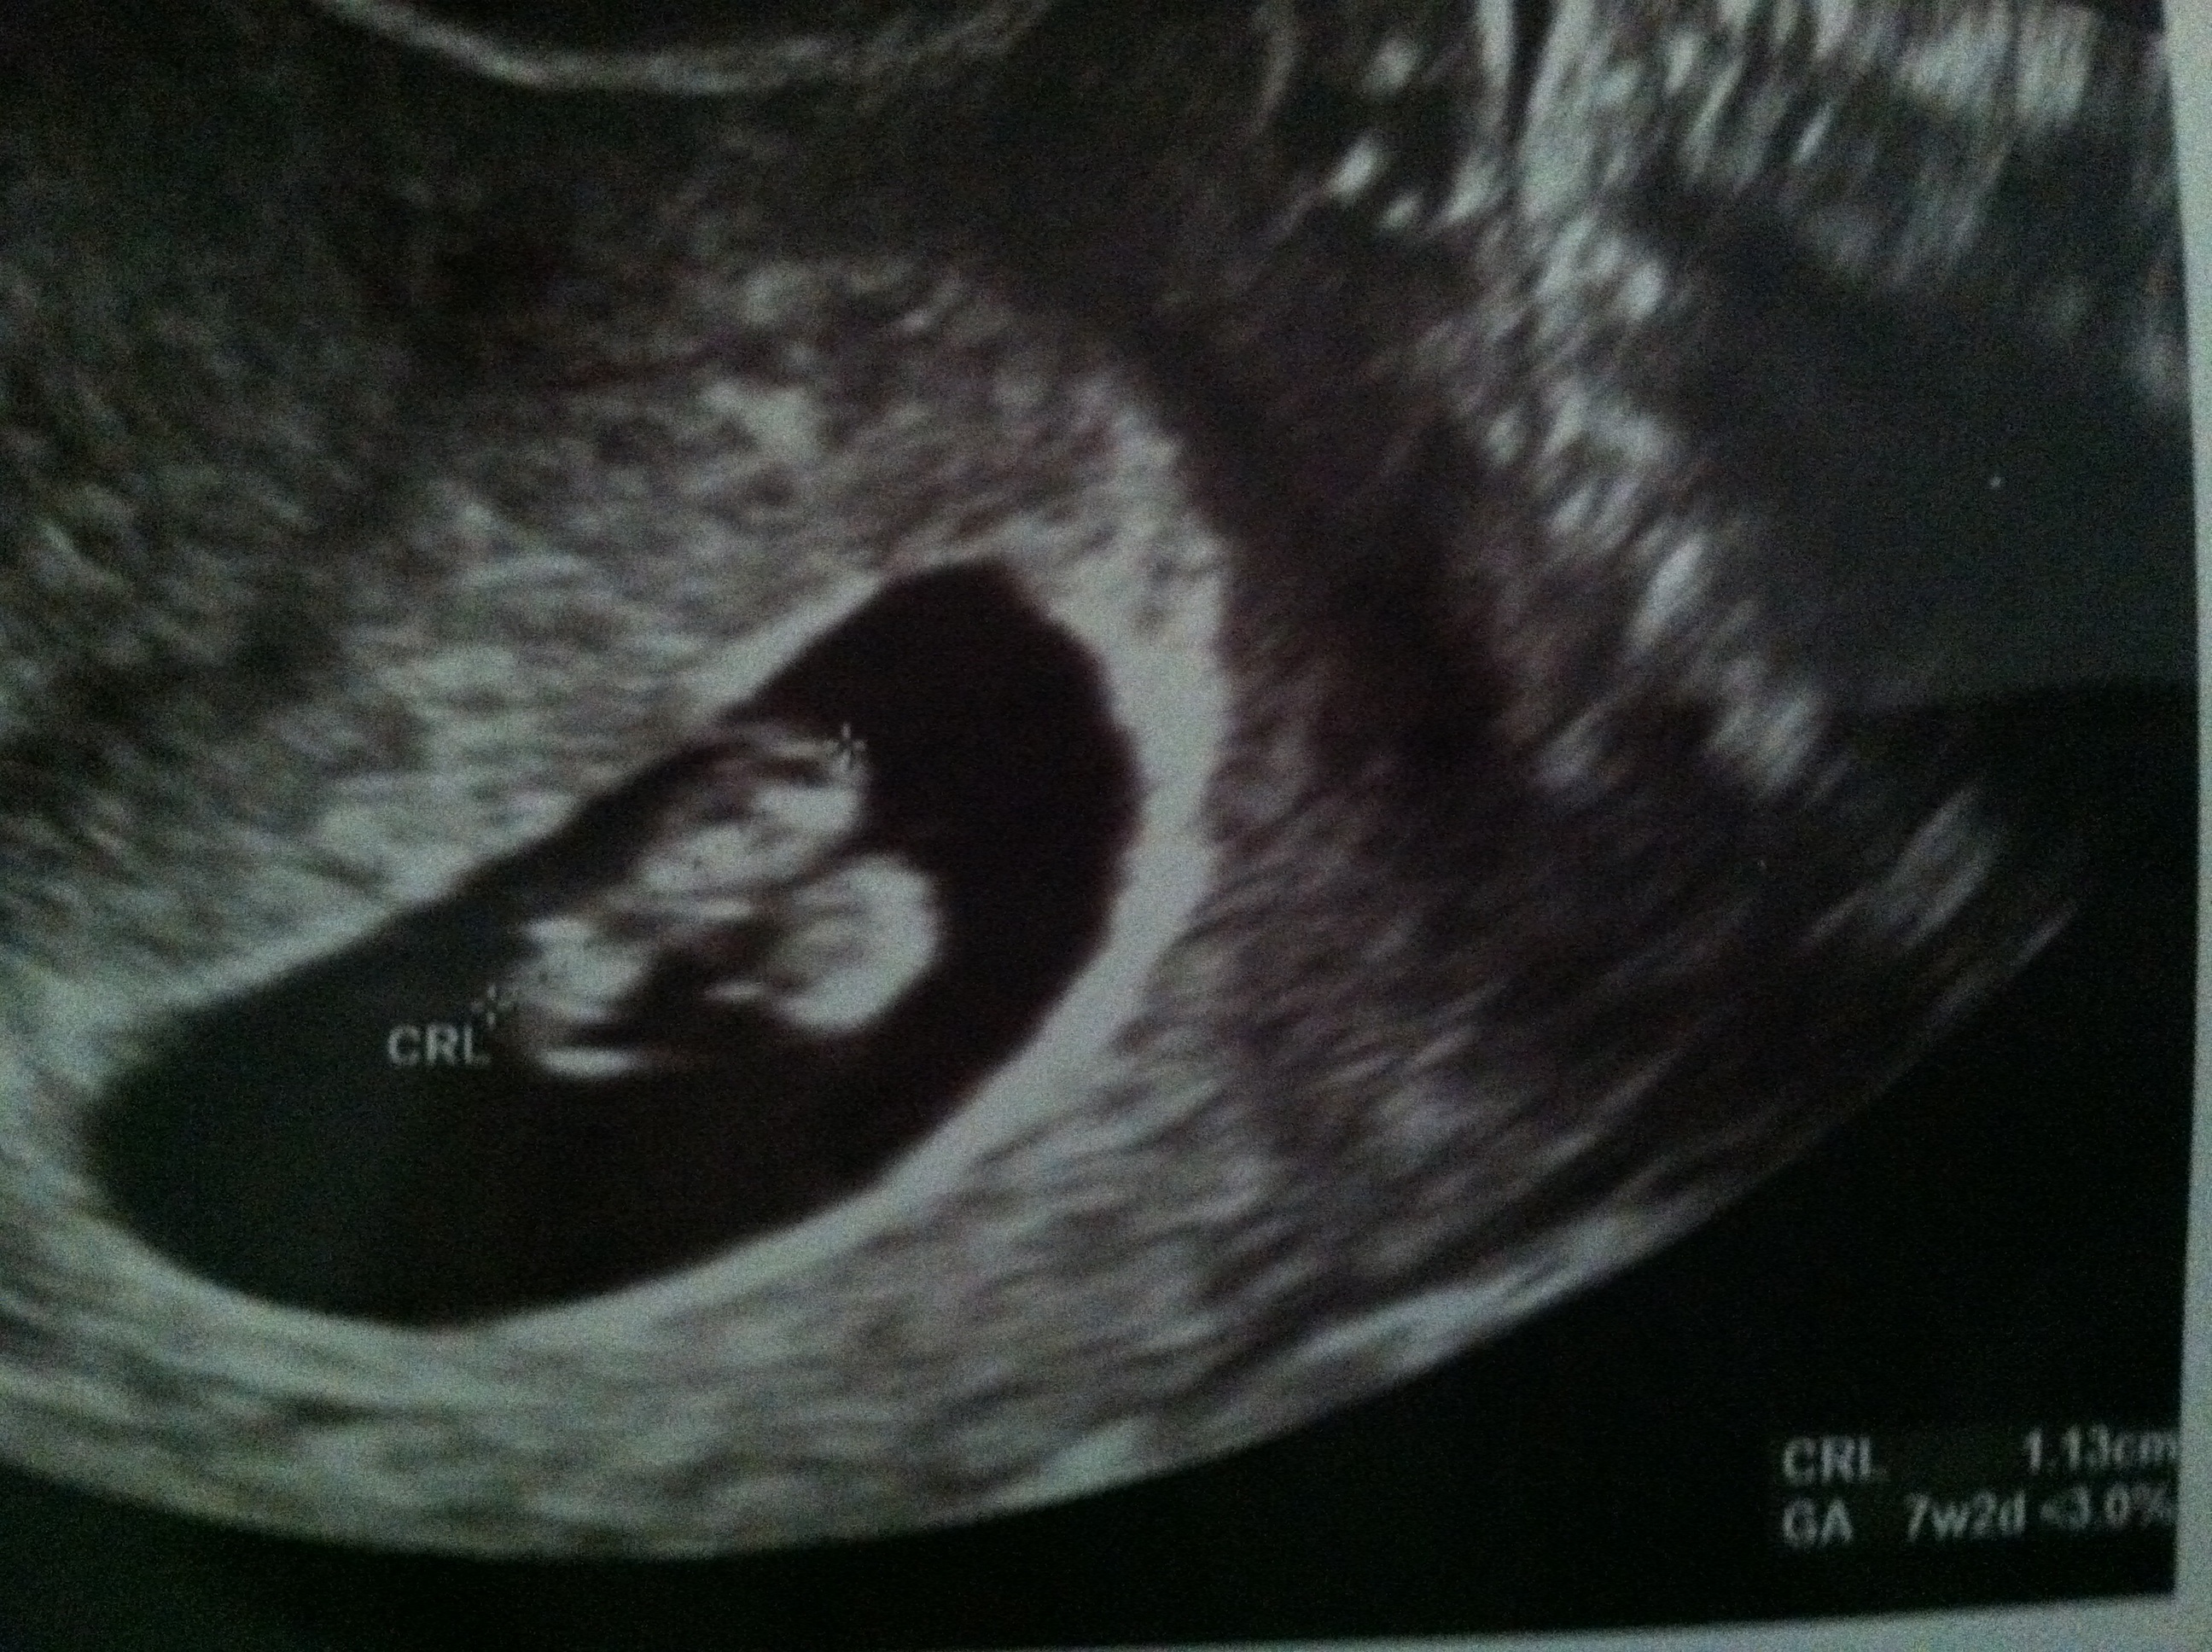

We saw our peanut!

I thought I turned 8 weeks today, but the ultrasound showed 7 weeks and 2 days.. Now I am paranoid (even though the doctor said baby is healthy and normal).. We saw the heart beating away.. I have never felt so much excitement.